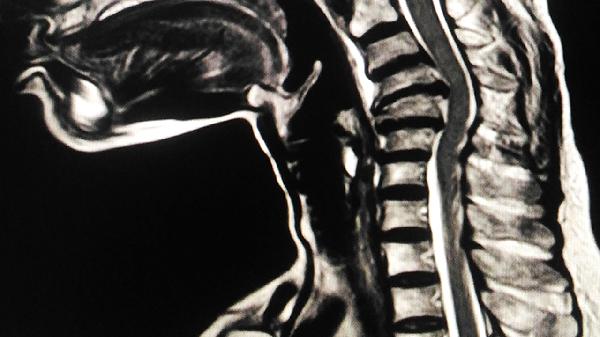

3、腰椎间盘突出

腰椎间盘向左后方突出可能压迫神经根,引起放射性疼痛,伴随下肢麻木或无力。急性期需卧床休息,使用甲钴胺片、塞来昔布胶囊、乙哌立松片等药物营养神经和消炎。严重者需行椎间孔镜手术。